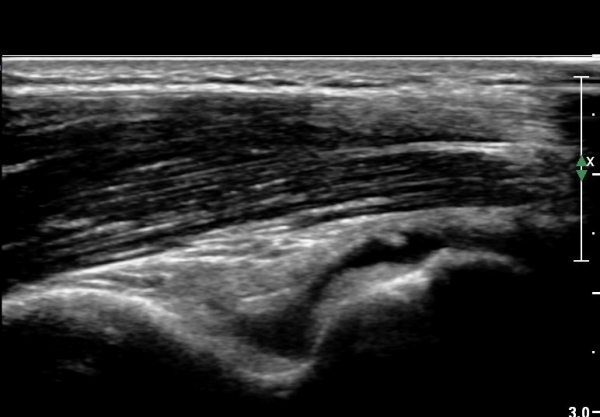

ŽÃËÀÚ¸¦ ¾à°£ ¿ÜÃøÀ¸·Î À̵¿ÇÏ´Ï °Ë ºÎÂøºÎ¿Í ÀÎ´ë ºÎÂøºÎÀÇ  ¹Ì¼¼ÇÑ ÆÄ¿­ÀÌ °üÂûµÈ´Ù(»çÁø 3).